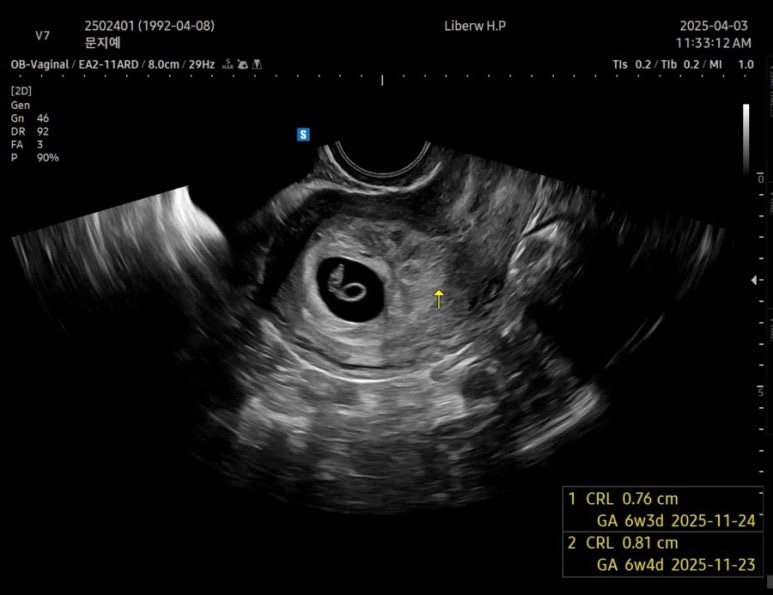

2일만에 쑥쑥커서 0.76cm가 된 사탕이🍬

장비가 좋아서 그런지 초음파가 엄청 선명하다!

드디어 6주 !!!!

예정일은 11월 24일로 변경

차뇨리랑 같이 들은 사탕이 심장소리

튼튼하게 잘 뛰고 있었다

심장박동수는 136bpm

많이 커진 난황 👼🏻